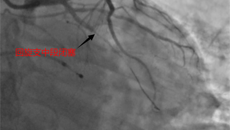

急性心肌梗死是心血管急危重症,一旦发生,患者心脏随时可能停跳。此时,时间就是心肌,时间就是生命,能否在2~3小时内及时开通被堵塞血管,对病情至关重要。 近日,广西国际壮医医院心病科便成功抢救了一名急性心肌梗死患者。心病科主任徐先增表示,抢救成功的关键不仅在于抢救本身,更在于“双绕行”(绕行急诊抢救室、绕行心病科监护病房)急救流程的正确实施。 65岁患者突发胸痛,国壮医生迅速诊断 一个多星期前,65岁的杨...08.302023